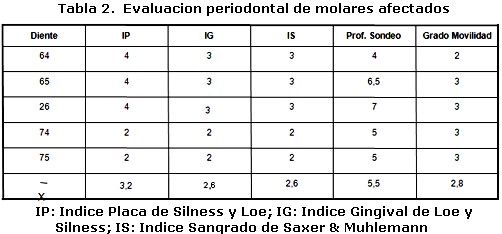

Un varón de tres años de edad con diagnostico de Histiocitosis de Células de Langerhans con afección ósea multifocal y otros sitios especiales fue referido al Servicio de Odontopediatría del Hospital Universitario de Maracaibo por el Servicio de Oncología Pediátrica del mismo Hospital, para valoración. El examen médico reveló, exoftalmos, palidez mucocutánea con pápulas eritematosas, lesiones hipercrómicas en miembros inferiores, dermatitis seborreica en cuero cabelludo, múltiples adenopatías cervicales y otitis supurativa recurrente. El informe de las pruebas de laboratorio indicó anemia y diabetes insípida. La biopsia de cuero cabelludo y el estudio inmunohistoquímico de la muestra tomada (Figura 1, 2 y 3) confirmaron el diagnóstico clínico, mientras que el examen de líquido cefalorraquídeo y médula ósea reportaron ausencia de infiltración. En las imágenes de resonancia magnética cráneo-facial, se evidenció realce anormal sugestivo de infiltración de huesos de base craneana y fosa anterior y media, mientras que la tomografía axial computarizada, reportó ausencia parcial de arco cigomático del lado derecho e imágenes osteolíticas en hueso temporal y pared orbitaria externa del mismo lado, acompañadas de lesiones similares en techo de orbita del lado izquierdo (Figura 4). Otros estudios, como tomografía de abdomen, pelvis y tórax, electroencefalograma, Rx de huesos largos, tórax óseo y columna, no revelaron hallazgos de interés. Durante la evaluación odontológica, la exploración extraoral evidenció exoftalmos y las lesiones de piel antes descritas; intraoralmente se registró la presencia de placa dental, gingivitis y hemorragia (Tabla 1), acompañada de movilidad dental, bolsas periodontales y recesión gingival (Figura 5) en la zona posterior izquierda de ambos maxilares (Tabla 2), además de caries dental y erupción prematura del 26. Radiograficamente se observaron lesiones osteolíticas, de bordes mal definidos, que medían aproximadamente entre 0,5 y 1,5 cm. de diámetro, localizadas en relación al 64, 65, 26, 74, 75, 85, también se observó agenesia de los gérmenes del 35 y 45 (Figura 6). Para el momento de la evaluación odontológica el paciente estaba recibiendo tratamiento con vasopresina y quimioterapia con vinblastina y prednisona. El manejo odontológico incluyo una fase inicial preventiva en la cual se instruyo a los representantes y al niño sobre hábitos de alimentación, higiene bucal y técnicas de cepillado y una fase quirúrgica llevada a cabo bajo anestesia general. Previa valoración sistémica y premedicación con antibioticoterapia se realizaron exodoncias del 65, 26, 74, 75 y curetaje de las lesiones. El resultado de la biopsia del tejido encontrado en los maxilares reportó un infiltrado inflamatorio severo, constituido por acumulo de linfocitos, histiocitos espumosos y células plasmáticas, mientras que el estudio inmunohistoquímico realizado con proteína S-100 y CD1a resultó negativo. Después de dos meses de seguimiento, el paciente cicatrizó favorablemente con persistencia en el 64 de recesión gingival, exposición de dos tercios de la raíz distal y movilidad leve. Radiograficamente se observan signos de osificación en las zonas intervenidas, sin embargo, es necesario seguir monitoreando al paciente para descartar la aparición de nuevas lesiones (Figura 7).

La Histiocitosis es una rara enfermedad cuyas manifestaciones clínicas son muy variadas; en el caso reportado, las características clínicas coinciden con algunas típicamente descritas en la literatura en relación a la edad, dermatitis seborreica, diabetes insípida, exoftalmos y lesiones óseas multifocales1-4. Este último tejido es uno de los más afectados1, nuestro paciente presentó lesiones en ambos maxilares y de forma bilateral en mandíbula, aunque en mayor grado del lado izquierdo. Desde el punto de vista clínico estas lesiones pueden semejar enfermedad periodontal y provocar movilidad dental2, la afectación ósea en nuestro paciente provocó erupción prematura del 26, recesión gingival y grado severo de movilidad dental; situación agravada por la presencia de irritantes locales. Un hallazgo que no hemos podido constatar con la literatura revisada, es la ausencia de los gérmenes del 35 y 45 sin relación con historia familiar, la cual podría catalogarse como agenesia, ya que de acuerdo a la secuencia y cronología dental, a los tres años edad deberían observarse signos de su formación7. Por otra parte, la ausencia bilateral de los gérmenes y la presencia de importantes lesiones osteolíticas solo en relación al 35, descarta la posibilidad de que las células infiltrantes hayan sido responsables de hallazgos similares en el lado contralateral donde la lesión era inferior a 0,5 cm. Sin embargo, es necesario descartar otros factores responsables de la agenesia dental antes de definir su etiología. El estudio inmunohistoquímico realizado a la lesiones intraorales no reveló positividad para S-100 y CD1a, a pesar de haberse encontrado positivos en la biopsia a inicial de cuero cabelludo. Estos marcadores además del CD207 han sido catalogados como específicos para la determinación de células de Langerhans; sin embargo se ha reportado hasta un 13% de resultados negativos para CD1a y un 7% para el CD2078. Los resultados obtenidos en la inmunohistoquímica de las lesiones maxilares, también podrían estar relacionados con los efectos producidos por la quimioterapia sobre las células infiltrantes. No obstante otros factores relacionados con la toma de la muestra no pueden descartarse como responsables de estos hallazgos. La decisión de seleccionar la cirugía, quimioterapia y/o radiación como tratamiento en la histiocitosis, dependen de la extensión de las lesiones, el grado de tejido involucrado y de la presentación unifocal o multifocal1,3. En este caso se decidió realizar exodoncias de los dientes con grado de movilidad severa y curetaje, con el fin no solo de tratar las lesiones maxilares sino de controlar el riesgo de infección. Se concluye que los maxilares al igual que los huesos del cráneo deben ser evaluados en pacientes con diagnóstico de Histiocitocis de Células de Langerhans, ya que estos pueden ser los únicos huesos afectados como sucedió en el caso estudiado. Por otra parte es importante resaltar que a pesar de la importancia de las pruebas inmunohistoquimicas en el diagnostico de esta enfermedad, su resultado siempre debe ser correlacionado con los hallazgos clínicos, radiográficos e histológicos encontrados en cada caso en particular.